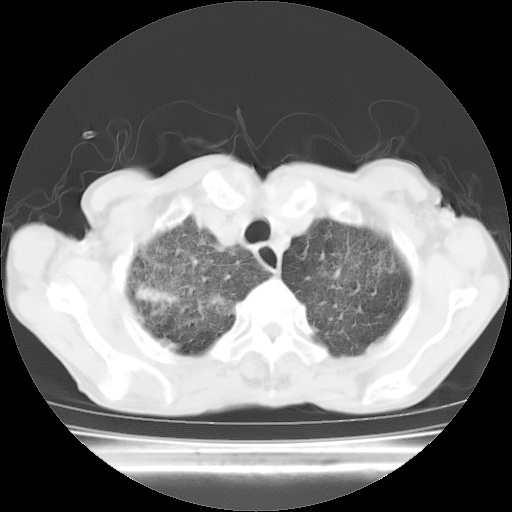

病人发热、气促就诊。原二周前已行ct扫描,当时诊断为双肺下叶、右肺中叶支气管扩张并感染,双肺上叶片状渗出性病变。今天复查胸部ct,双肺下叶支气管扩张并感染病灶较前明显吸收,但双肺上叶渗出性病变较范围较前明显增大。

现传今天ct图像给大家讨论。

双肺多发大片状、斑片状高密度渗出影,部分实变,考虑病毒性肺炎。